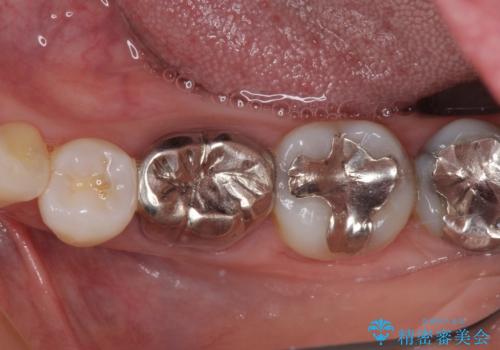

- 口を開けたときに目立ってしまう銀歯をセラミックに替えたいとのことで来院された患者様です。

上顎や親知らずにも銀歯がありましたが、今回の治療では目立つ下顎の銀歯4歯をセラミッククラウンやセラミックインレーに置き換えることにしました。